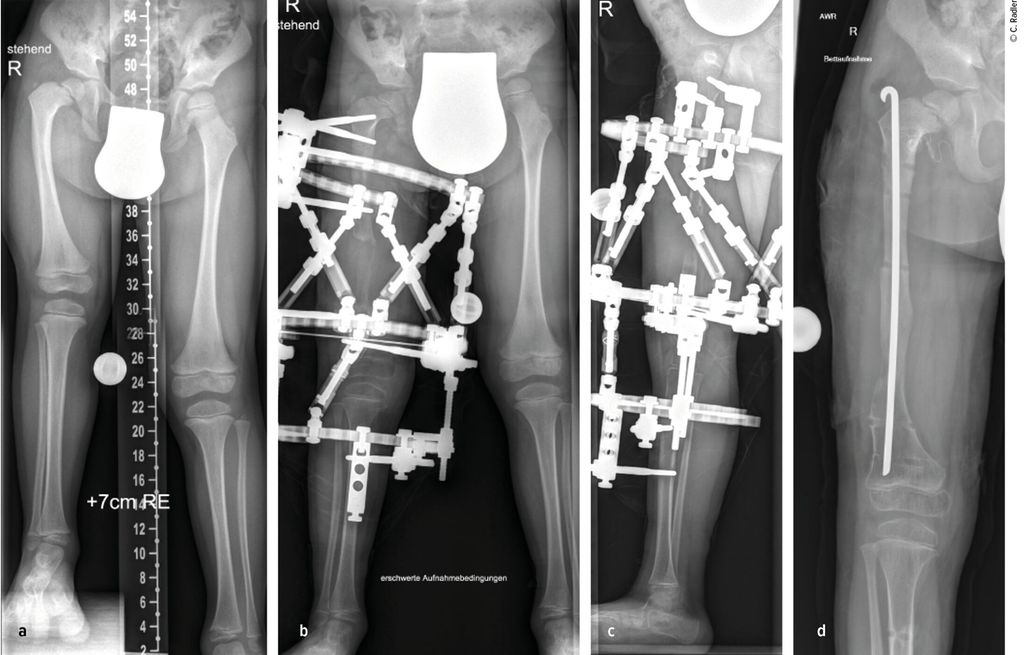

Pathologie am Kniegelenk

Die Valgusstellung kann sehr einfach über eine Wachstumslenkung (Hemiepiphysiodese mit 2-Loch-Platte) korrigiert werden. Um eine Subluxation am Kniegelenk zu verhindern, muss bei allen diesen Fällen bei Verlängerung mit Fixateur dieser knieüberbrückend montiert werden (Abb.4). Bei Verlängerung über einen Verlängerungsmarknagel wird in diesen Fällen eine Oberunterschenkelschiene (KAFO) verwendet und prophylaktisch, soweit noch vorhanden, die Fascia lata auf Höhe des oberen Patellapols durchtrennt. Bei deutlicher Instabilität oder auch Subluxation ist eine Stabilisierung über eine komplexe Operation, die als Super-Knee-Operation subsumiert wird, erforderlich.2 Diese Operation kann auch an die Hüftrekonstruktion/Super-Hip-Operation angeschlossen werden, da hier die Faszie ohnehin präpariert wird. Je nach Alter des Patienten und dem Ausmaß der Instabilität wird hierbei die Fascia lata nach Präparation bis an das Tuberculum Gerdyi und Halbieren der Länge nach entweder extraartikulär oder intraartikulär geführt. Auch die Fixation wird abhängig vom Alter mit Biotenodeseschrauben oder Weichteilzügelung durchgeführt.

Der kongenitale Femurdefekt sowie auch die anderen longitudinalen Längsdefekte sind hochkomplexe angeborene Fehlbildungen, bei denen das Verständnis der Pathologie und Anatomie die Voraussetzung für eine rekonstruktive Therapie darstellt. Die genannten Operationstechniken adressieren die vielgestaltigen Gelenkspathologien sowie die knöchernen Deformitäten. Die Knochenverlängerung ist in diesem Behandlungskonzept nur einer der notwendigen Schritte, um am Ende neben einem Längenausgleich eine funktionelle und belastbare untere Extremität zu erzielen.